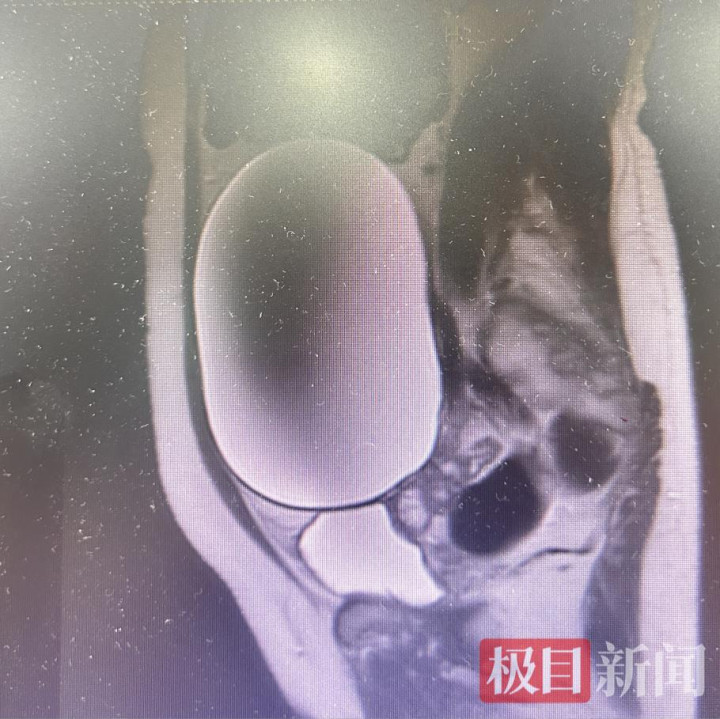

“此次齐也曾来病院了,不如作念个彩超检查下,宽解点。”在老伴的建议下,陈女士趁便作念了全身检查,没思到这一查竟查出了大问题。检查成果领路,她的盆腔右侧有一个大小约178毫米×96毫米×158毫米的囊性包块,左侧附件区还有一个37毫米×45毫米的囊性包块,其中右侧包块直径约18厘米,堪比一个小西瓜大小。11月21日,陈女士被转入妇科二病区进一步调整。

患者体内的盛大包块